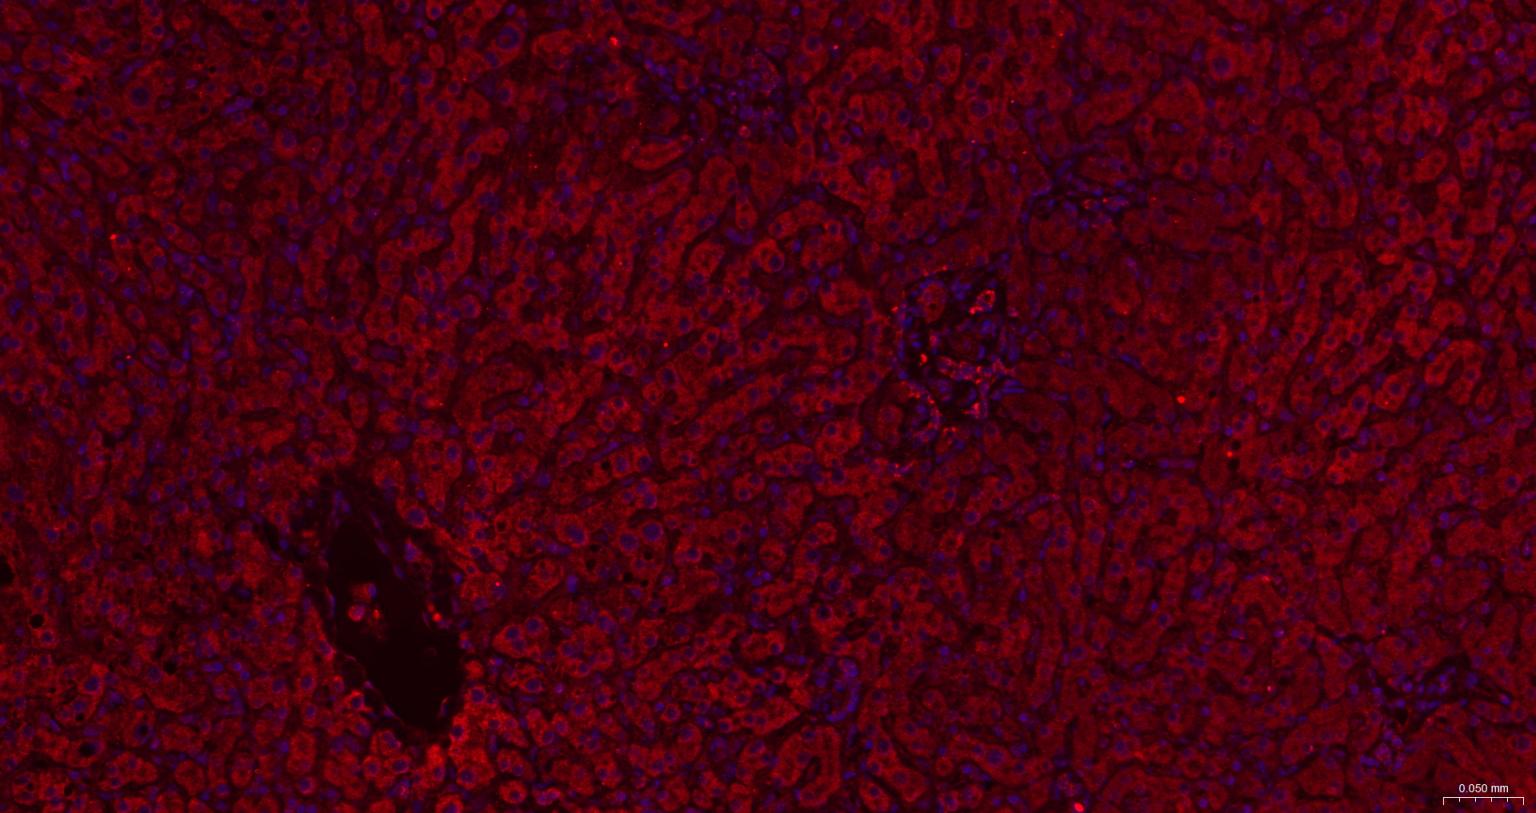

Paraformaldehyde-fixed, paraffin embedded Human Liver; Antigen retrieval by boiling in sodium citrate buffer (pH6.0) for 15 min; The section was incubated with IRE1 Polyclonal Antibody, Unconjugated (bs-8680R) at 1:200 overnight at 4°C. Followed by conjugated Goat Anti-Rabbit IgG antibody (Red, bs-0295G-BF594), DAPI (blue, C02-04002) was used to stain the cell nuclei.